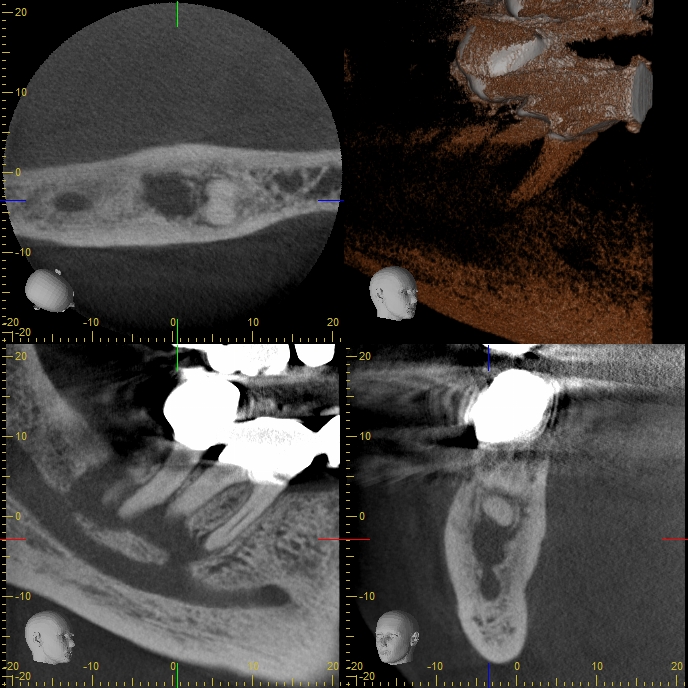

XYZView_20120402_132242 Veröffentlicht 8. April 2013 am 688 × 688 in Was zeigt das DVT (2) – Die Auflösung